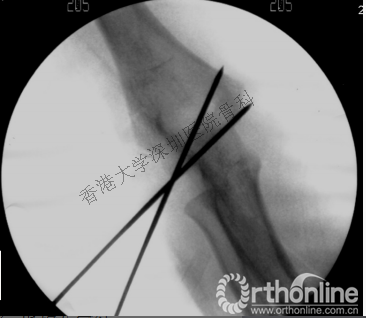

女,4岁,跌伤致右肘疼痛,X片示右肱骨外髁骨折。因肱骨外髁处软骨较多,骨折极易漏诊。

术中X片

因此,认识到在x片中,很多儿童的骨骺部分是软骨,并不能充分显像,选择合适的辅助检查,在治疗过程中需要考虑儿童的成长,做出正确的诊断,就显得尤为重要。

手法复位后不稳定的II型及III型骨折需行经皮克氏针固定。外髁两枚克氏针或内外侧各一枚克氏针交叉克氏针固定均可,两针在骨折线平面相距越远则固定越稳固,应避免在骨折线平面交叉。